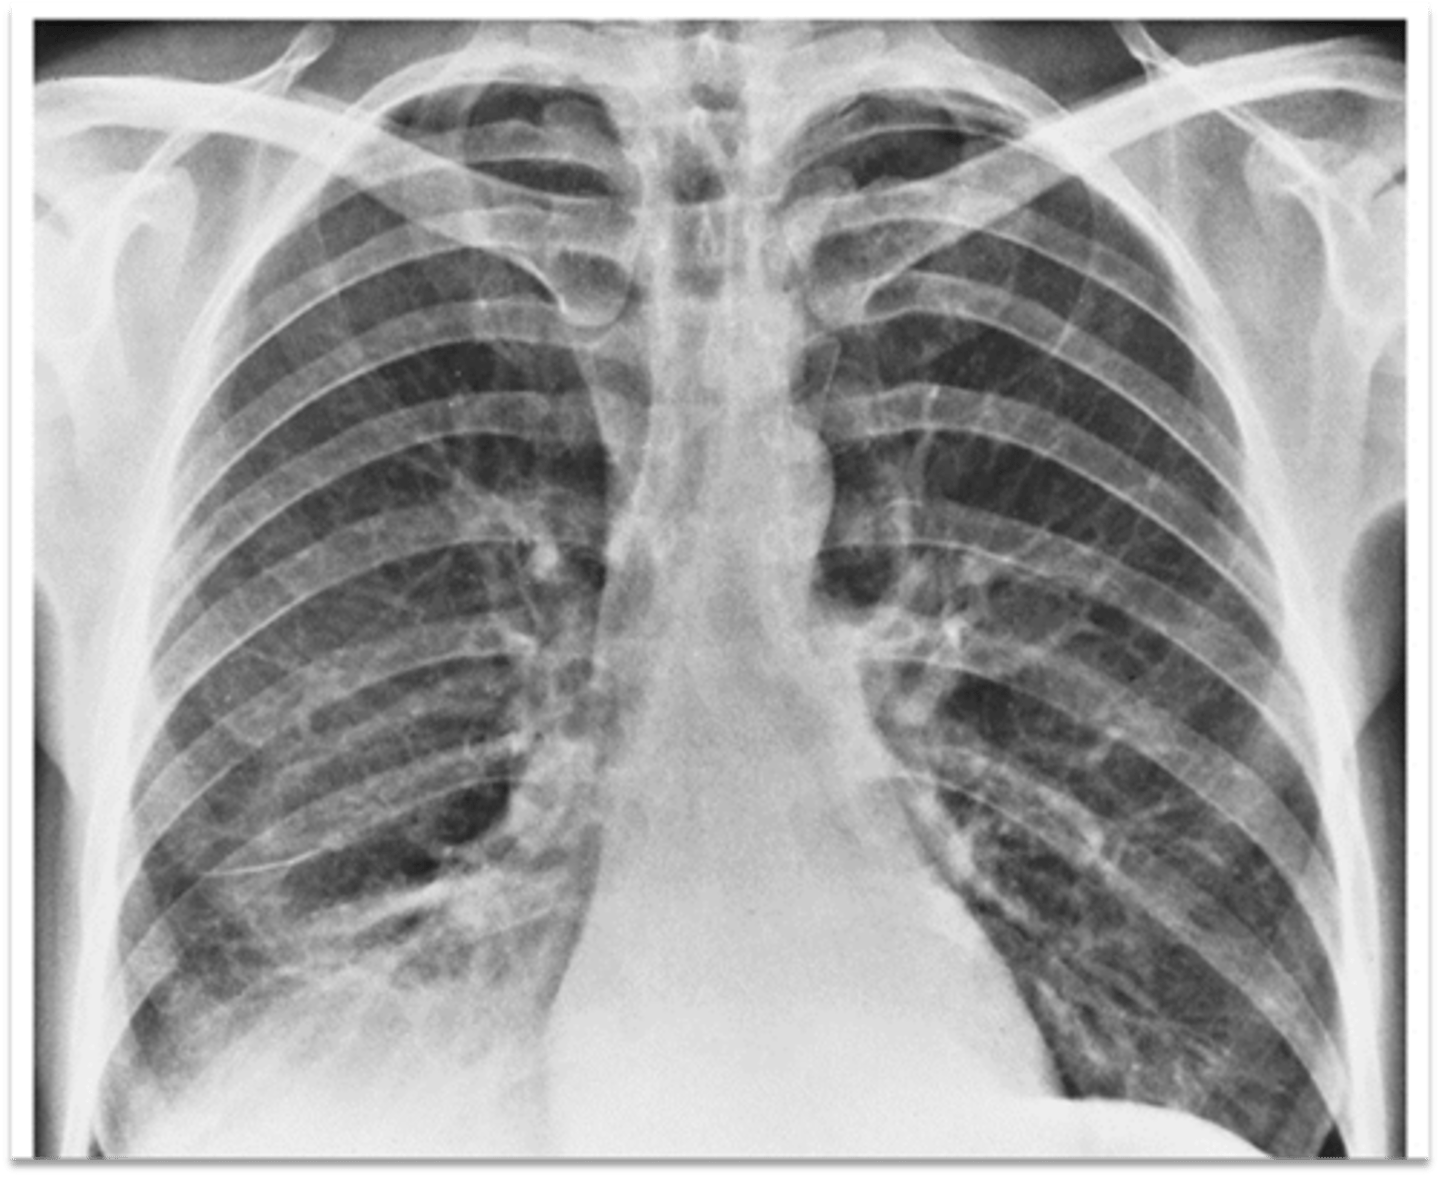

Possible CHF (presence of Kerley B lines)

What does the chest film show?

CHF (Kerley B lines- short, horizontal white lines that indicate fluid accumulation)

Interpretation?